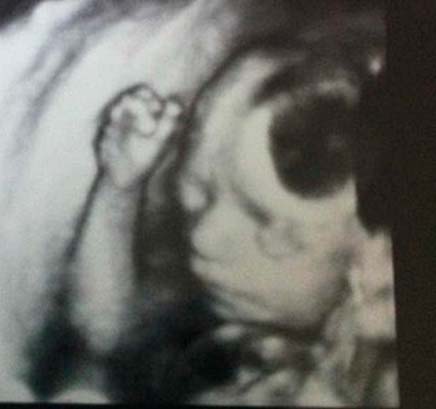

Voici à quoi ressemble le fœtus à 24 semaines:

À ce moment, l'échographie est rarement prescrite. Mais si vous allez à cette étude, vous pouvez certainement voir le visage de votre enfant. Ses caractéristiques ne changeront pas jusqu'à la naissance même.

Photo échographie: